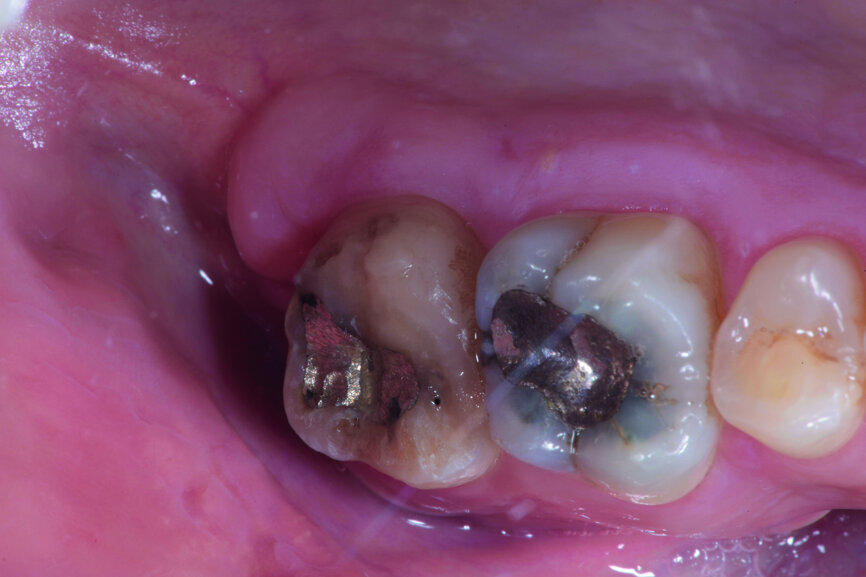

Fig. 14d: Clinical image: Control after one month.

Fig. 17d: Clinical images: Eight-year recall.

The left mandibular second molar of a 35-year-old female patient had been compromised because of a vertical root fracture and a large periapical lesion was present. After explanation and informed consent, the treatment was scheduled. The right mandibular third molar was preferred as a donor to the left mandibular third molar because of a more compatible anatomy and for an easier stabilisation. After local anaesthesia of both the donor and the recipient sites with 2 per cent mepivacaine with 1:100,000 adrenaline, the left mandibular second molar was extracted and the alveolus debrided. Then the donor tooth was atraumatically extracted, quickly repositioned in the recipient site and stabilised with sutures at about 1.5–2.0 mm of infraocclusion. An antibiotic (amoxicillin/clavulanic acid, 1 g, by mouth twice a day for five days) and a non-steroidal anti-inflammatory drug (ibuprofen, 600 mg, by mouth twice a day for five days) were prescribed, along with rinses with 0.2 per cent chlorhexidine. The sutures were removed after two weeks and endodontic treatment was performed after three months. The periapical lesion healed and the tooth was fully functional after 12 years (Figs. 14a–d & 15a–d).

A 23-year-old female patient presented with a vertical root fracture of tooth #47. Tooth #48 was transplanted to site #47. The tooth was fully functional after eight years (Figs. 17a–d & 18a–d).